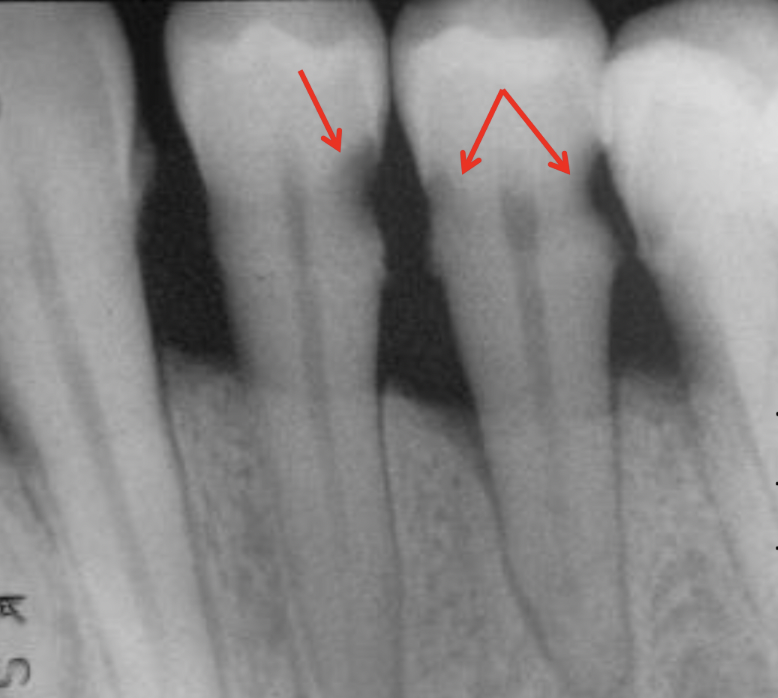

What is going on in the following radiograph?

Severe occlusal caries